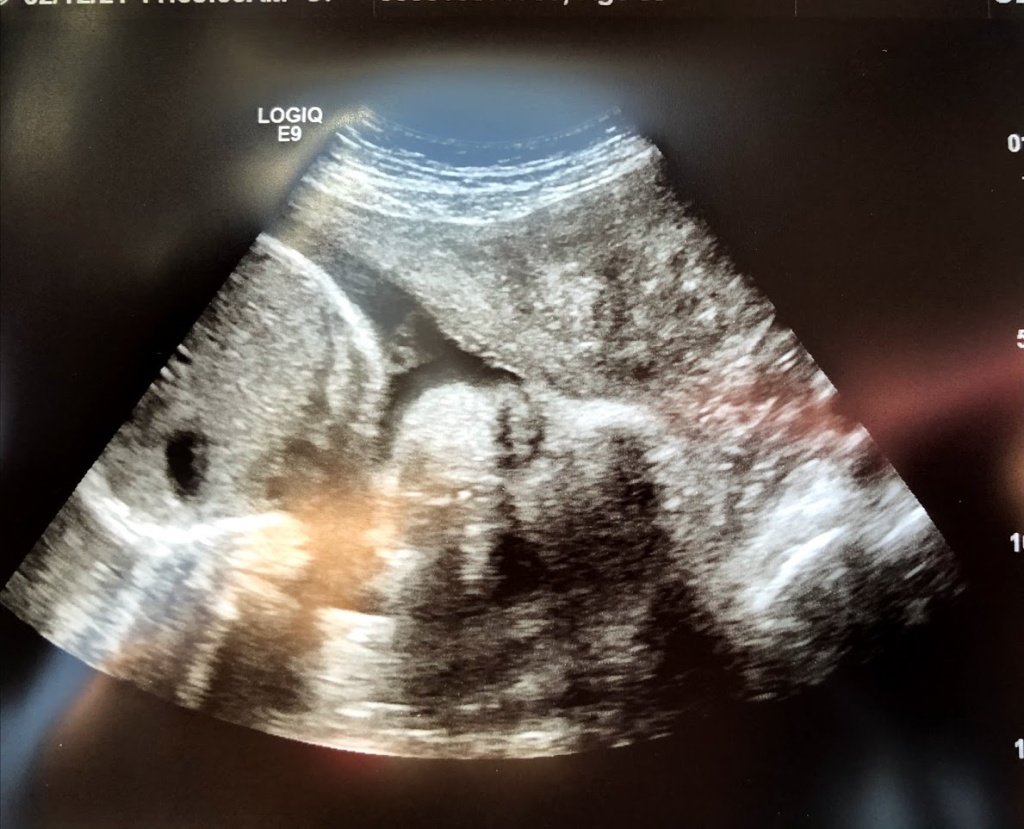

Ultrasound at 31 weeks.